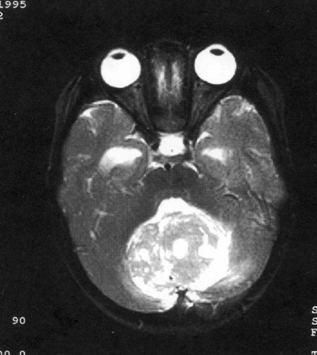

问题 病历摘要:??患儿男性,11岁。半年前开始出现行走不稳,常无故跌倒。半月前出现发作性剧烈头痛,伴恶心呕吐。体检:T36℃,P100次/分,R22次/分,BP100/60mmHg,神清,言语较缓慢,双眼外展约不及边,双眼侧视时有小幅度水平眼震。四肢肌力正常,右上肢肌张力较低,坐位姿势不稳,常不自主摇晃,双上肢指鼻不准,行走蹒跚步态,足距扩大,身前倾。 下一步应首先采取哪些措施?提示:多次缝合伤口,仍有脑脊液渗漏。